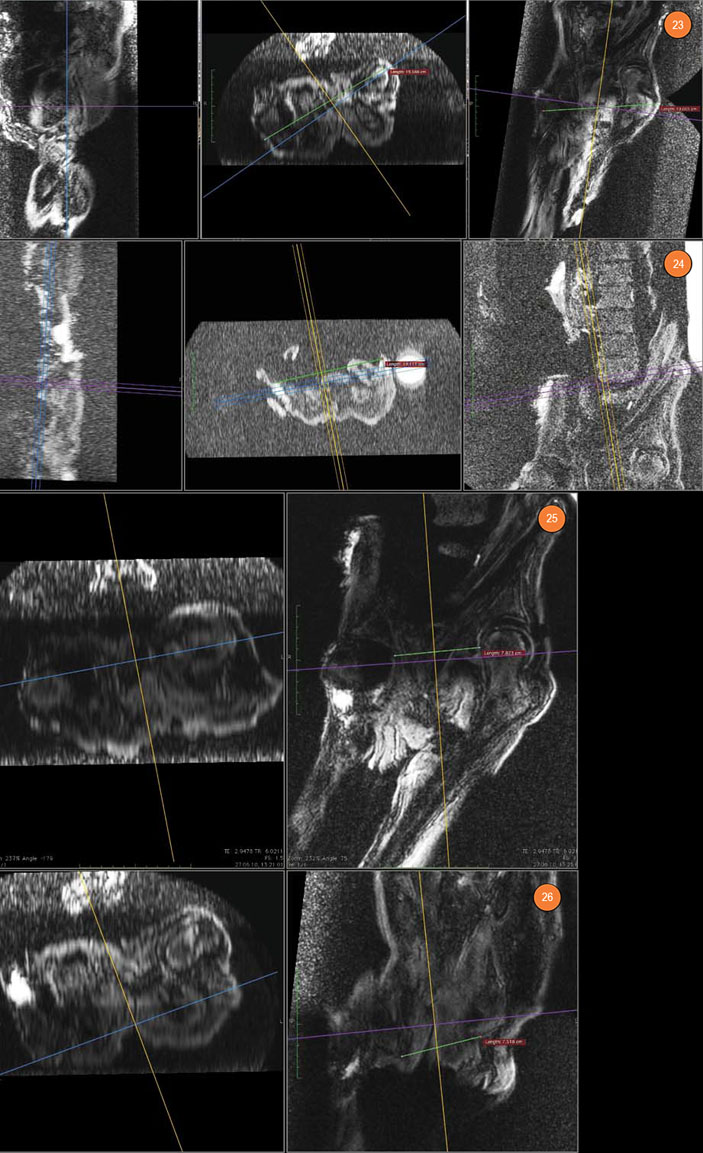

Рис. 21. Левый тазобедренный сустав. Рис. 22. Правый тазобедренный сустав. А — имеется резкая отечность в области шейки и в межтрохантерной зоне (внутри сустава, видна «пустая» гленоидальная полость), Б — головка бедренной кости вывихнута за пределы края гленоидальной полости

Капсула этого сустава имеет явную отечность со скоплениями жидкости внутри суставной капсулы, с выраженной отечностью в прилежащей клетчатке правой паховой области. Именно эти данные позволяют утверждать, что изменения правого тазобедренного сустава носят прижизненный характер. В сочетании с травматической деформацией головки правой плечевой кости, деформацией передней крестообразной связки правого коленного сустава (о которой речь пойдет ниже) и деформации поясничного отдела позвоночника по типу сублистеза они дают основания предположить значительную прижизненную травму. Это могло произойти при падении с лошади.

Поскольку пояс нижних конечностей у мумии при томографии находился не в ортогональной позиции, для измерения размеров малого таза пришлось использовать технологию 3D MPR.

Расстояние между большими вертелами бедренных костей оценено в 19 см, но, учитывая вывих правого тазобедренного сустава, можно говорить о том, что при жизни оно было равно 23,0–23,5 см (современная норма — 30–31 см). Расстояние между передними верхними остями подвздошных костей составило 19 см (современная норма — 25–26 см).

Поскольку измеренные наружные размеры малого таза мумии значительно отличаются от нормы, а размеры черепа ее самой и ее взрослых современников и современного человека схожи, то закономерно встает вопрос о размерах полости малого таза. Его размеры — принципиально важный вопрос для деторождения, поскольку малый таз представляет собой костную часть родового канала: его задняя стенка состоит из крестца и копчика, боковые образованы седалищными костями, а передняя — лобковыми костями и симфизом.

Рис. 23. Измерение distantia intertrochanterica. Рис. 24. Измерение distantia interspinalis. Рис. 25. Измерение поперечного размера плоскости широкой части малого таза. Рис. 26. Измерение поперечного размера плоскости выхода из малого таза

Размеры малого таза у мумии оказались гораздо меньше, чем у современных женщин. Опираясь на современные акушерские нормы, можно говорить о III степени суженности таза, при которой невозможны естественные роды (в современных условиях показано кесарево сечение). С другой стороны, нельзя полностью исключить возможность деторождения. Можно предположить эволюцию биомеханики родов, поскольку строение крестца у мумии отличается от современного: межпозвонковые диски не утрачены — по-видимому, крестцовый отдел позвоночника был достаточно подвижен и только 2–3 верхних крестцовых позвонка являли собою единый крестец. Вполне возможно, что такое строение крестца компенсировало узость родового канала. Не исключено также, что в те времена у молодых особей соединения между костями таза могли быть более подвижными, чем в наши дни, поскольку репродуктивный возраст начинался у них уже в начале второго десятилетия жизни при ее средней продолжительности в 30–40 лет. Более того, в условиях относительно ограниченных пищевых ресурсов рождение крупного потомства было маловероятным.